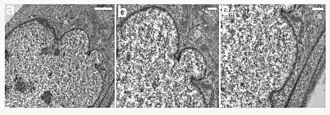

A young girl with progeria (left). A healthy cell nucleus (right, top) and a progeric cell nucleus (right, bottom). | |

HGPS is caused by mutations that weaken the structure of the cell nucleus, making normal cell division difficult. The histone mark H4K20me3 is involved and caused by de novo mutations that occur in a gene that encodes lamin A. Lamin A is made but is not processed properly. This poor processing creates an abnormal nuclear morphology and disorganized heterochromatin. Patients also do not have appropriate DNA repair, and they also have increased genomic instability.[14]

In HGPS, the recognition site that the enzyme requires for cleavage of prelamin A to lamin A is mutated. Lamin A cannot be produced, and prelamin A builds up on the nuclear membrane, causing a characteristic nuclear blebbing.[37] This results in the symptoms of progeria, although the relationship between the misshapen nucleus and the symptoms is not known.

A study that compared HGPS patient cells with the skin cells from young and elderly normal human subjects found similar defects in the HGPS and elderly cells, including down-regulation of certain nuclear proteins, increased DNA damage, and demethylation of histone, leading to reduced heterochromatin.[38] Nematodes over their lifespan show progressive lamin changes comparable to HGPS in all cells but neurons and gametes.[39] These studies suggest that lamin A defects are associated with normal aging.[38][40]